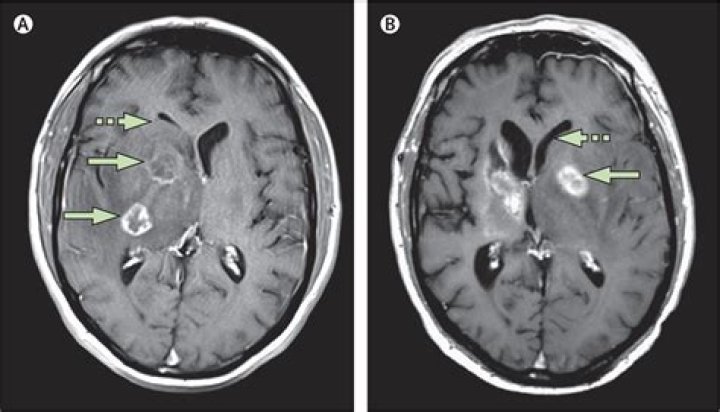

Cerebral toxoplasmosis is usually caused by reactivation of the latent cystic form of T. gondii in the central nervous system (CNScentral nervous system (...